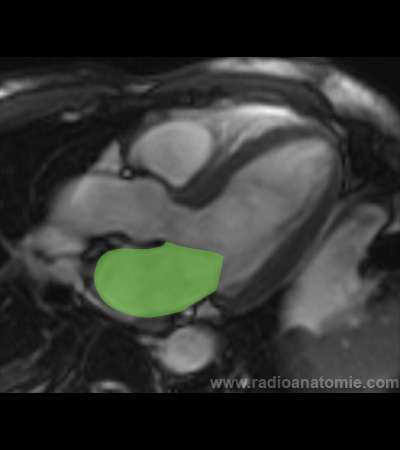

Ventricule gauche